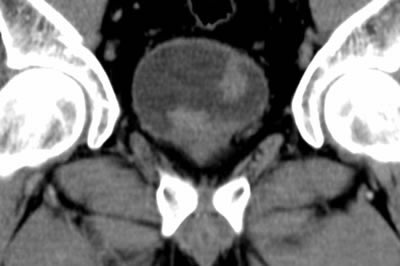

СКТ (Спиральная компьютерная томография)

СКТ (Спиральная компьютерная томография) . Рак мочевого пузыря.

• КТ таза – увеличение до 1,5 см одного лимфоузла в области

• запирательной ямки слева